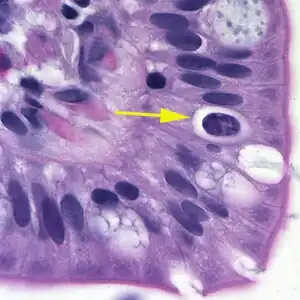

| Oocistos de Cystoisospora em célula epitelial (H&E). | |